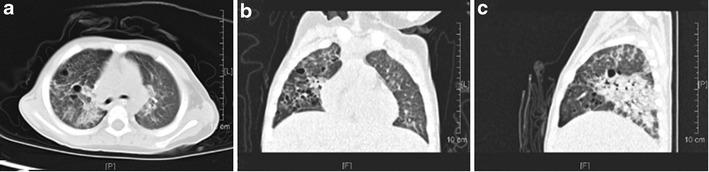

The study group consisted of 23 boys (69.7 %) and 10 girls (30.3 %), with ages ranging from 4 mo to 4 y. They were admitted to the hospital 2 h to 13 d after ingesting the oil-based substance. By the time of admission, most patients presented with respiratory distress and other symptoms, including tachypnea (n = 21), cough (n = 25), mild fever (n = 18), progressive dyspnea (n = 12), and pneumorrhagia (n = 5); six patients received mechanical ventilation because of complicated respiratory distress syndrome. The most common laboratory observations were leukocytosis (25 of 33, 75.8 %), neutrophilia (23 of 33, 69.7 %), and anemia (8 of 33, 24.2 %). Serum biochemical examination showed elevated sedimentation rates (24 of 33, 72.7 %), lactate dehydrogenase levels (18 of 33, 54.5 %), and C-reactive protein levels (17 of 33, 51.5 %). The most common finding on computed tomography (CT) scans was areas of consolidation. Within the follow-up duration of 2 wk to 6 mo, all patients with clinical symptoms of ELP experienced remission, and none died. The CT scans of most of the cases were normal by 1 to 3 mo, except for two patients who showed complete improvement 6 mo after treatment.

研究组包括23例男孩(69.7%)和10例女孩(30.3%),年龄范围为4个月至4岁。他们在摄入油性物质后2小时至13天入院。入院时,大多数患者表现为呼吸窘迫及其他症状,包括呼吸急促(n = 21)、咳嗽(n = 25)、低热(n = 18)、进行性呼吸困难(n = 12)及肺出血(n = 5);6例患者因并发呼吸窘迫综合征接受机械通气。最常见的实验室检查结果为白细胞增多(33例中的25例,75.8%)、中性粒细胞增多(33例中的23例,69.7%)及贫血(33例中的8例,24.2%)。血清生化检查显示血沉升高(33例中的24例,72.7%)、乳酸脱氢酶水平升高(33例中的18例,54.5%)及C反应蛋白水平升高(33例中的17例,51.5%)。计算机断层扫描(CT)最常见的表现为实变区。在2周至6个月的随访期内,所有有ELP临床症状的患者症状均缓解,无死亡病例。大多数病例在1至3个月时CT扫描结果正常,2例患者在治疗6个月后完全恢复。